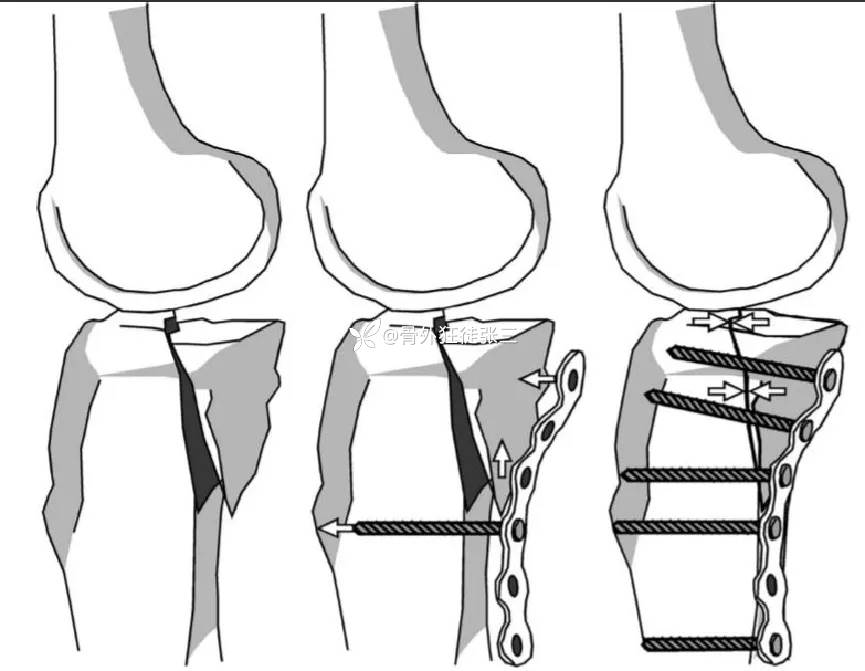

下图为罗从风教授主编的

胫骨平台骨折一书

关于手术入路